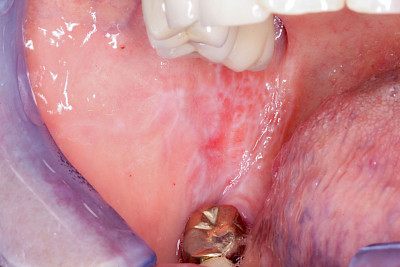

Leukoplakie, Erythroplakie

Die Auffälligkeiten sind zurückzuführen auf gestörte bzw. überschießende, z. T. entzündliche Stoffwechselvorgänge im Bereich der Schleimhäute.

Bei der sogenannten Leukoplakie handelt es sich um eine Hyperkeratose (Hornhautbildung), die auch entarten kann (fakultative Präkanzerose).

Nach dem Erscheinungsbild werden verschiede Typen unterschieden:

- Plan (Leukoplakia simplex bzw. plana): homogen-weiß, meist klar begrenzt, Oberfläche glatt. Entartungsrisiko 0–3 %

- Warzenartig (Leukoplakia verrucosa): homogen-weiß, meist klar begrenzt, Oberfläche warzig. Entartungsrisiko 11–20 %

- Erosiv (Leukoplakia erosiva): inhomogen weiß mit roten Anteilen. Entartungsrisiko ca. 30–38 %

Demgegenüber hat die Erythroplakie als homogen-rötliche Erscheinung (häufig mit einem weißlichen Anteil im Randbereich) ein deutlich erhöhtes Entartungsrisiko, weshalb man hier auch von einer obligaten Präkanzerose beziehungsweise einem Carcinoma In Situ (CIS) mit invasivem Wachstum ausgeht – vor allem, wenn die Veränderung am Mundboden, am Zungenrand oder an der Zungenunterseite lokalisiert ist.

Neben mechanischen Reizen zählen auch Rauchen und Alkoholkonsum zu den möglichen Ursachen. Manchmal sind diese Veränderungen, etwa wenn die Auffälligkeit im Bereich der Wange oder auch der Zunge auf Höhe der Zahnreihe im Zubiss (Okklusionsebene) zu liegen kommt, auch auf Wangen- bzw. Zungenkauen als Ursache zurückzuführen. Die beobachtbaren Veränderungen reichen hier von diskreten homogen-weißlichen Strichen (Linea alba) bis hin zu erosiv "unruhigen" Schleimhautarealen. Je nachdem, wie intensiv und wie ausdauernd und mit welcher Kraft diese Habits ausgeführt werden. Auch hier sollte auf eine Verhaltensänderung hingewirkt und ein Zahnarzt verständigt werden.